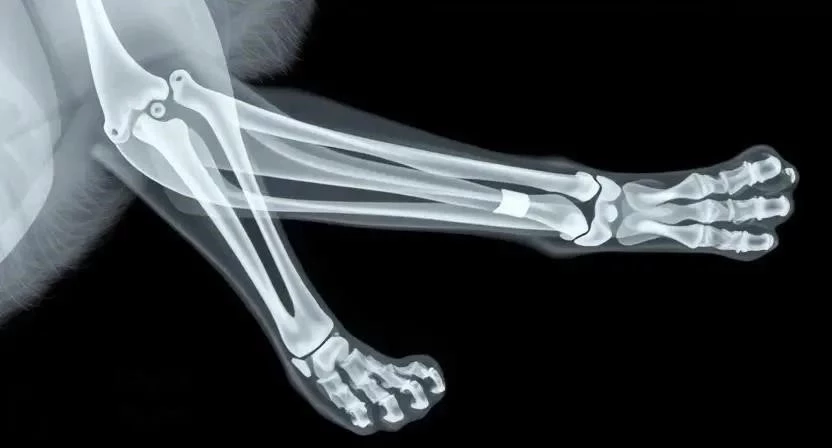

- Фиксация переломов и вывихов: Если вы подозреваете перелом или вывих, необходимо зафиксировать поврежденную лапу. Используйте шину из подручных материалов (например, картон или палка) и бинт. Транспортируйте кошку к ветеринару максимально осторожно.

- Диагностика: Ветеринар проведет диагностику, чтобы определить характер и степень тяжести травмы. Могут потребоваться рентген, УЗИ или анализы крови.

- Переломы: Лечение переломов зависит от их типа и сложности. В некоторых случаях достаточно наложить гипс, в других – может потребоваться операция.

Лечение переломов

| Тип перелома | Метод лечения | Длительность | Эффективность |

|---|---|---|---|

| Закрытый перелом | Гипс | 4-8 недель | Высокая |

| Открытый перелом | Операция, фиксация осколков | 6-12 недель | Средняя |

| Внутрисуставной перелом | Операция, фиксация сустава | 8-16 недель | Средняя |